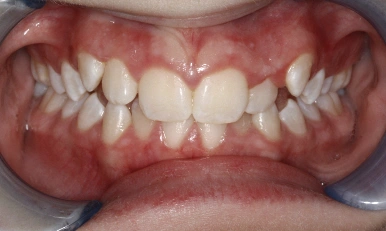

Patient Results